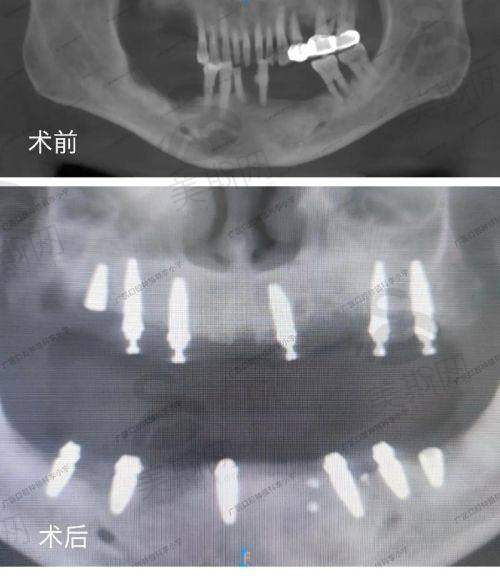

好多姊妹擔心「平嘢冇好嘢」,其實只要揀對診所,深圳種牙質素唔輸香港。重點睇3樣:①種植體來源(要有品牌授權書,比如Straumann官網可查代理商);②醫生經驗(更好揀有10年以上種植經驗,做過500例以上成功实例嘅醫生);③術後保护(正規診所會提供5 - 10年種植體保修卡,寫明脫落免費重做)。比如深圳格倫菲爾口腔,有香港醫生定期坐診,仲支持「香港CT報告直連」,唔使重複檢查,夠晒方便。

根據上海五官科醫院左翔等4位專家2025年審閱報告,主流品牌成功几率都超過95%,關鍵係揀啱自己。以下係香港人更鐘意嘅5個品牌對比:

瑞士Straumann 骨結合快(3 - 4周),表面處理先進,適合骨質差人士 預算充足,想長期穩定(用20年以上) 18000 - 30000 6580 - 12000(格倫菲爾口腔)

韓國Osstem 亞洲人顎骨設計,臨床实例多,穩定性好 後牙修復,預算中等(5 - 8萬半口) 8000 - 12000 3800 - 5500(玖藝口腔)

美國Nobel 即刻種植技術成熟,前牙美學成效靚 前牙缺損,對笑容要求高 20000 - 40000 8800 - 15000(護芽口腔)

韓國Dentium 癒合周期短(6 - 8周),操作簡便 想縮短治療時間(2個月搞掂) 7000 - 10000 3240起(蓮塘口岸牙科,約人民幣2980)